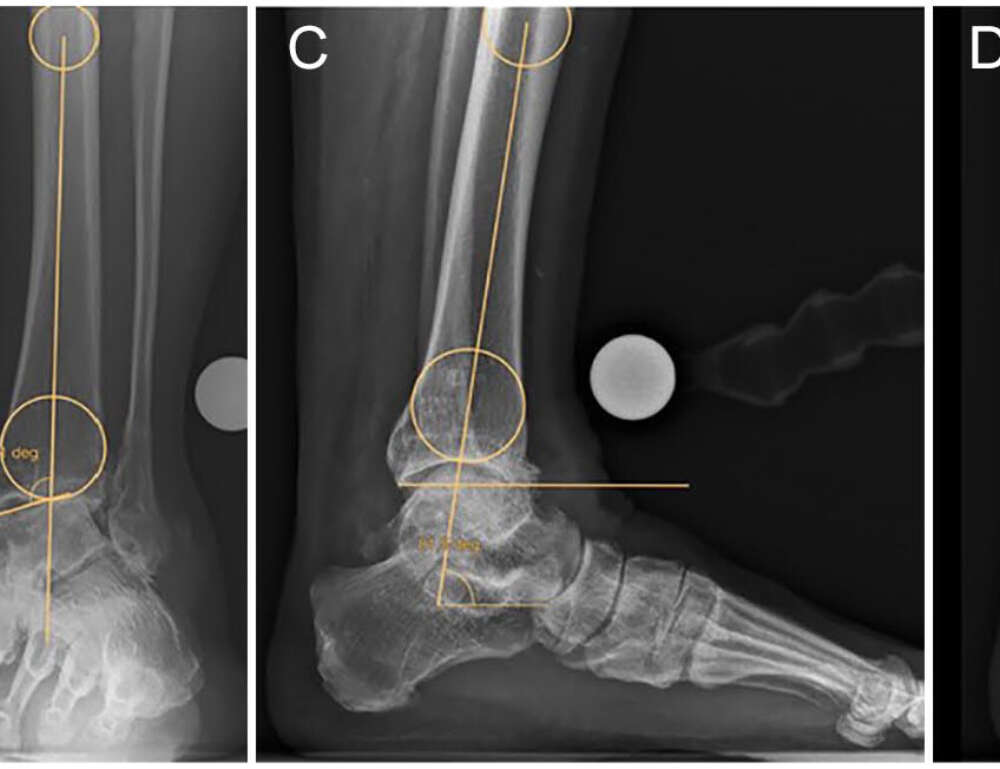

Die vorhandene Literatur zur Überlegenheit der patientenspezifischen Instrumentierung (PSI) bei der Knöchel-Totalendoprothese (TAA) gegenüber der Standardreferenzierung (SR) ist begrenzt. Als Vorteile werden unter anderem eine bessere Implantatausrichtung, kürzere Operationszeiten und eine höhere Genauigkeit bei der Vorhersage der Implantatgröße genannt. Ziel dieser retrospektiven Studie war es, die PSI in den Händen eines erfahrenen Fuß- und Sprunggelenkschirurgen zu analysieren, der sowohl mit der PSI als auch mit der SR für dieses spezielle Implantat noch nicht vertraut war, und zwar im Hinblick auf die Bestimmung der Implantatausrichtung, der Operationszeiten und des radiologischen Kurzzeitergebnisses sowie der Vorhersage der Implantatgröße für tibiale und talare Komponenten.